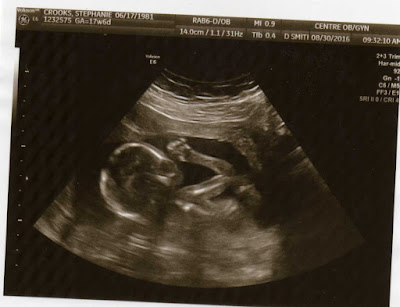

Week 18, Baby #2

My doctor's appointment went well yesterday. Everything looked good and nothing too exciting to report. They were unable to view one side of her heart due the gestational age, so they'll have me back in 2 weeks to get a better view/picture.

Here are a couple pictures from the appointment -

Addison loves looking at the pictures and even brought them to school today! I'm hoping those little ones don't ask too many questions!